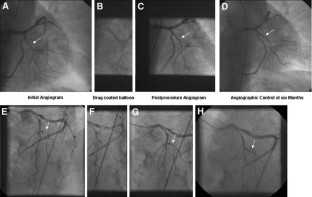

Eighty-two of 118 patients (70%) with a vessel diameter of 2.35 ± 0.19 mm were treated with the drug-coated balloon only, while 32 patients required additional stent deployment. The mean in-segment late lumen loss was 0.28 ± 0.53 mm. In patients treated with the drug-coated balloon only, the in-segment late lumen loss was 0.16 ± 0.38 mm. At 12 months, the rate of major adverse cardiac events was 15% which was primarily due to the need for target lesion revascularization in 14 patients (12%). In those with additional bare metal stent implantation geographical mismatch between coated-balloon dilatation and stent implantation was significantly associated with the occurrence of restenosis.

Fig. 2